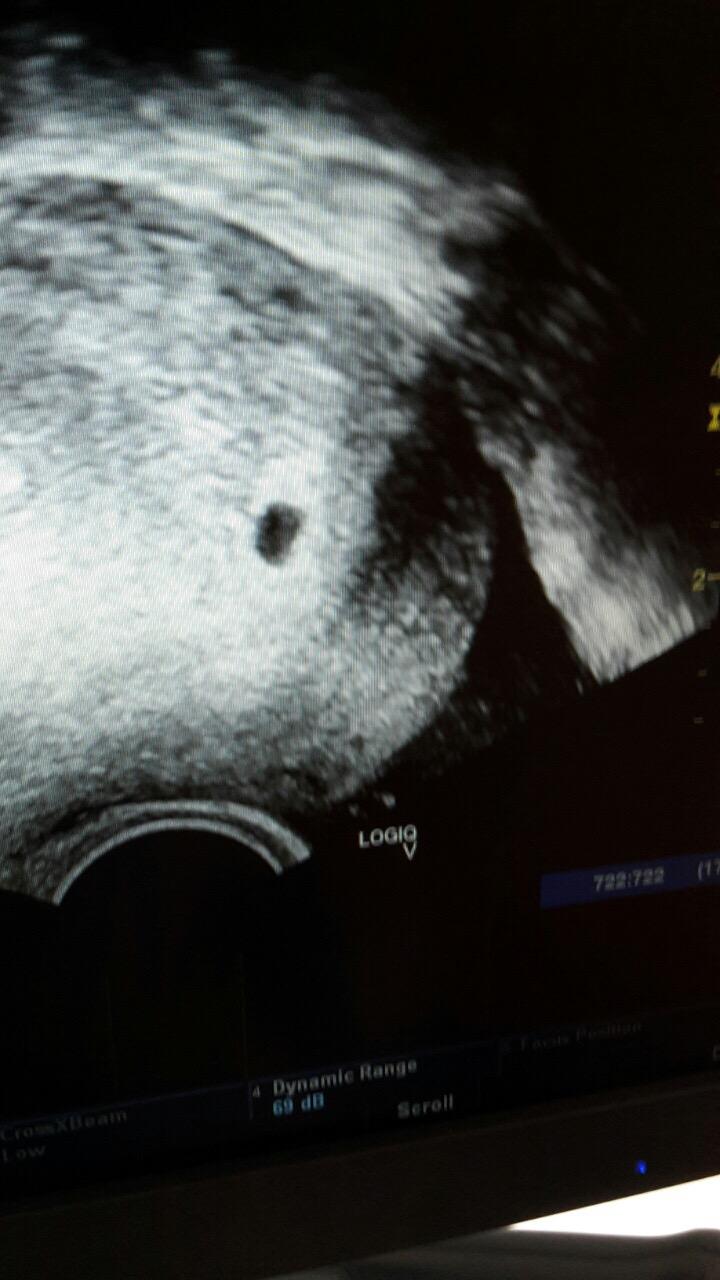

Tak jsem tu. Krvacim jasnou krvi, vcetne "cucku". Na UZ je videt nejaka tecka, mensi nez minule. Nabrali mi krev. Zitra nastupuju rano do spitalu, udela se dalsi kontrolni odber krve. Kdyz se jim to nebude zdat, ceka me revize a nasledne testovani, aby se vyloucilo mimodelozni. Ale pry je sance, ze pokud krvacim, odejde samo a pokud by bylo mimo, muze se vstrebat, pry je to male. Horecky za to nemuzou, doktorka rikala, ze dobre zalozene tehotenstvi to zvladne. Je mi blbe, jsem u taty, ti se staraji o malou. Ale ta mi nic neda zadarmo, rve jak tur, nevim proc.